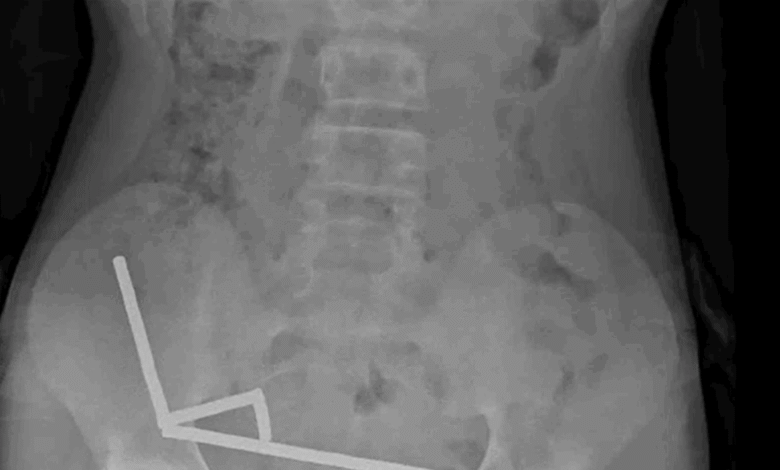

أظهرت صور الأشعة تجمع المغناطيسات في أربعة خطوط داخل الأمعاء “ملتصقة ببعضها بسبب القوى المغناطيسية”، ما سبّب تلفًا في الأنسجة.